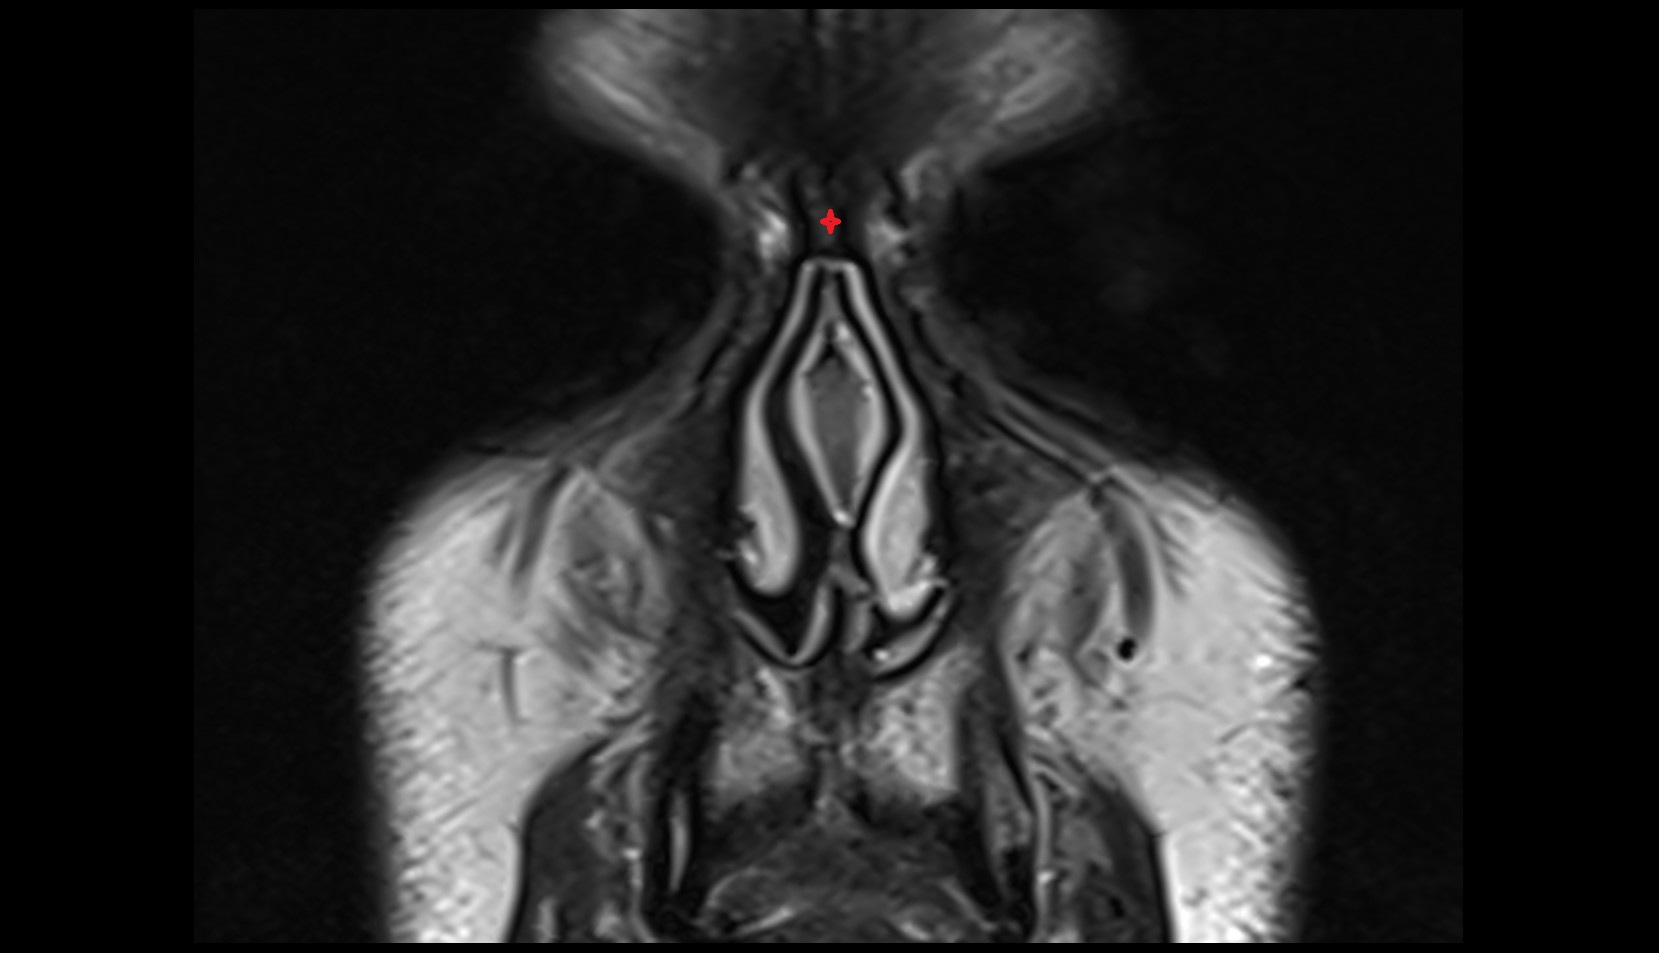

- Uterus

- Vagina

- Fornix of the vagina

- Endometrium of uterus

- Myometrium of uterus

- Perimetrium of uterus

- Junctional zone of uterus